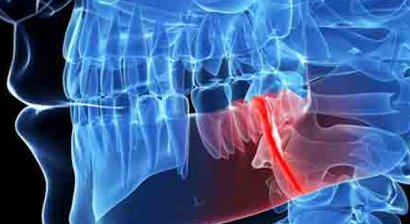

Der Weisheitszahn Der Weisheitszahn ist von der Mitte aus gezählt der achte Zahn im menschlichen Gebiss. Normalerweise hat ein Mensch vier Weisheitszähne, in jedem Gebissquadranten einen. Sie brechen meist erst im Erwachsenenalter, teilweise gar nicht durch. Die Anzahl der Wurzeln ist unte...